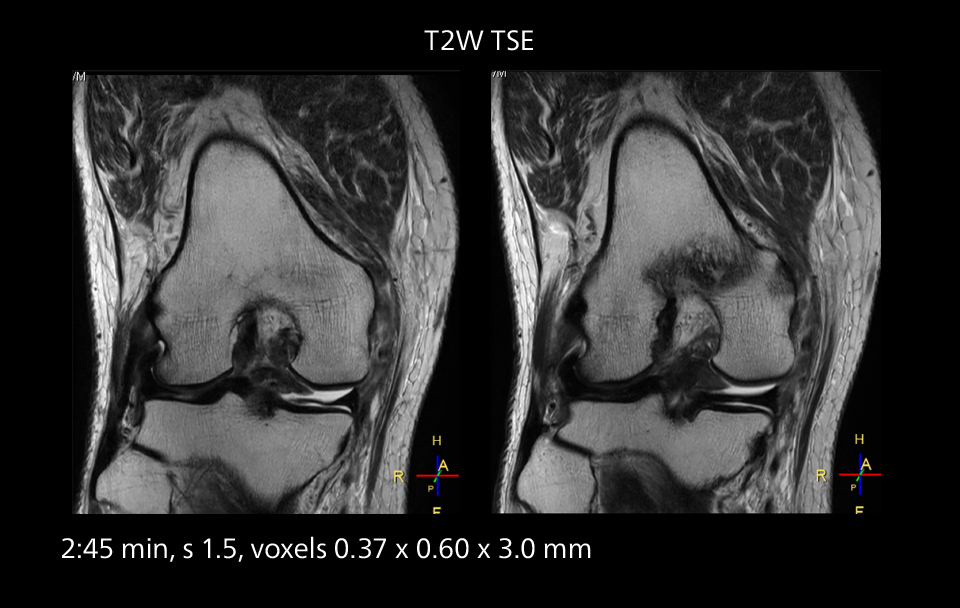

Images showing a posterior cruciate ligament (PCL) tear, a detached medial collateral ligament (MCL) on the tibial side and an intact anterior cruciate ligament (ACL). SmartPath to Elition X helped reduce scan time compared to previous imaging while maintaining resolution.